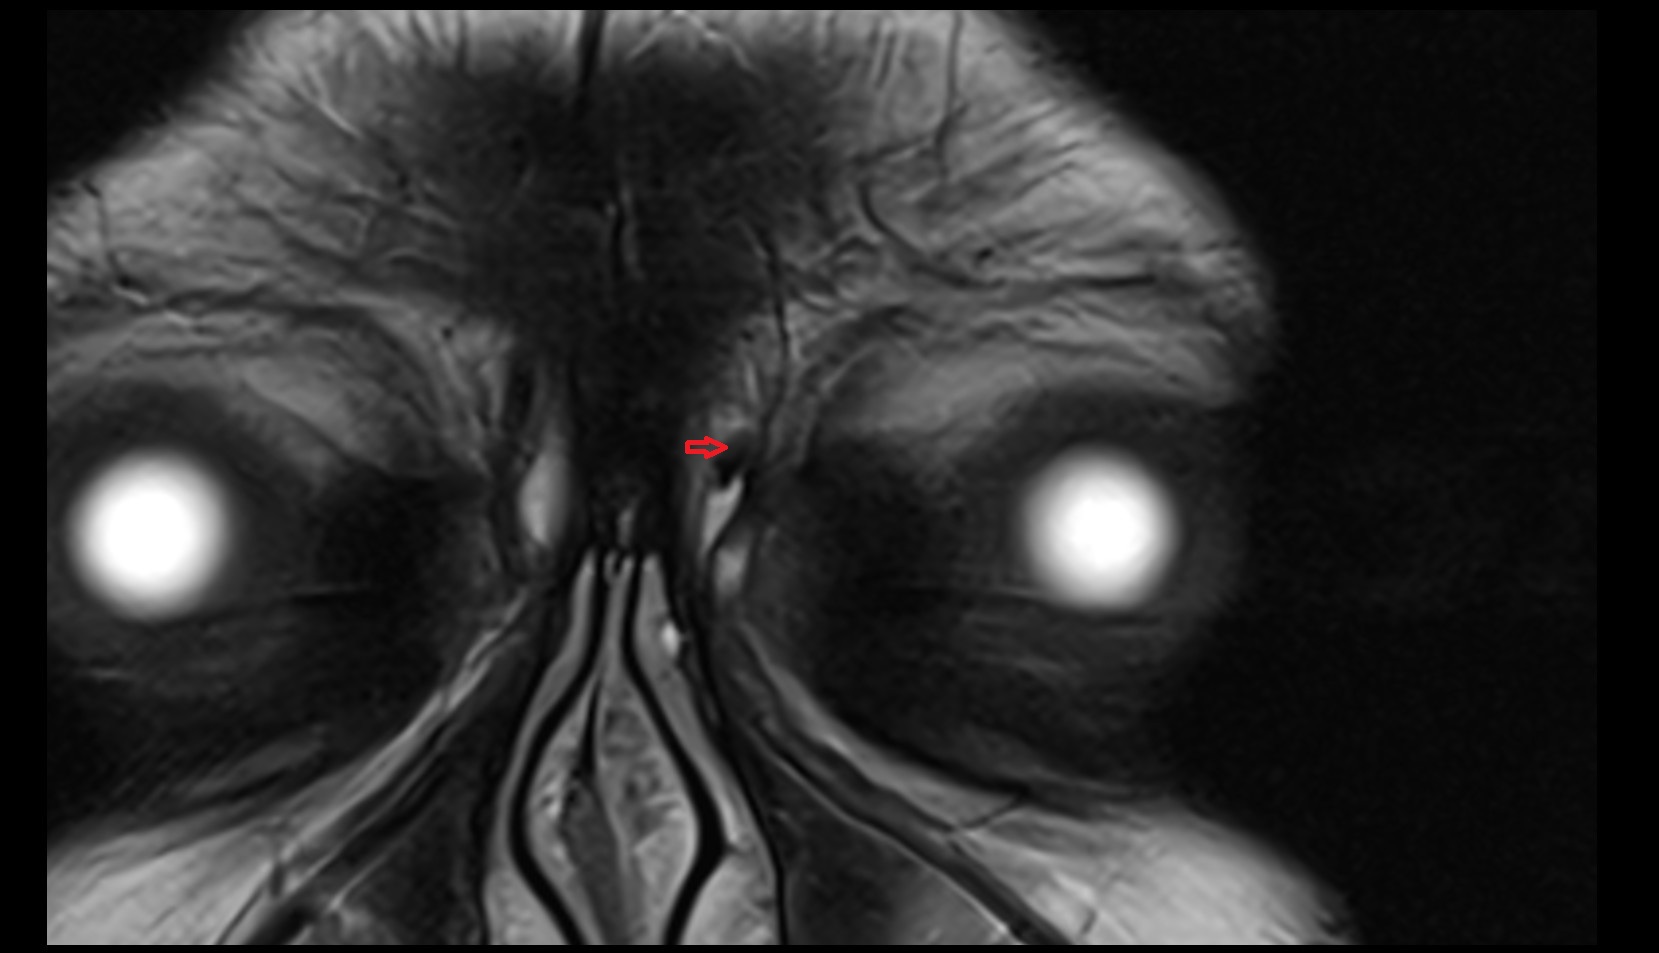

- Temporomandibular joint

- Mandibular condyle

- Mandibular fossa